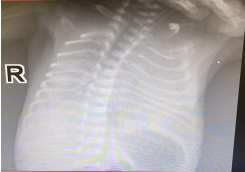

3月6日,新生儿科收治一名胎龄为31周,体重仅为1.13kg的新生儿,诊断为肺透明膜病、早产儿、极低体重儿。入院后予以肺内注入肺泡表面活性物质及呼吸机支持,该患儿入院后凝血功能差、水肿,予以改善凝血功能后,需要进一步静脉用药支持治疗。3月10日,取得患儿家长同意,儿科PICC团队在无菌技术下对该患儿进行了PICC置管,该患儿血管条件较差,置管过程中由于患儿贵要静脉血管走向不直,血管有转角,送管突发困难,专科护理老师用丰富的置管经验,立即通过轻柔牵拉患儿手臂皮下组织及肌肉位置,使血管走向转角减小,将PICC管路顺利通过转角,送达预定位置,行胸部DR 定位,PICC尖端位于第6肋,位置准确,置管成功。